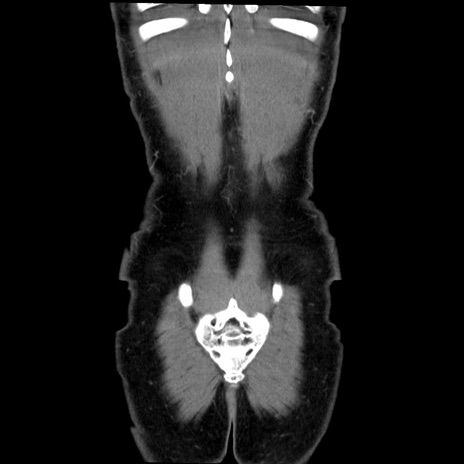

症例36(冠状断像)

【症例】20歳代 男性

【主訴】心窩部痛

【現病歴】今朝より上腹部痛あり。一旦軽快していたが再度出現したため救急要請。昨日夕に白身の魚を含む刺身を食べた。

【身体所見】BP 136/89mmHg、HR 74/min、BT 37.0℃、腹部:膨満、軟、心窩部に圧痛あり。反跳痛なし、筋性防御なし、腸雑音やや亢進あり。

【データ】WBC 17700、CRP 0.48